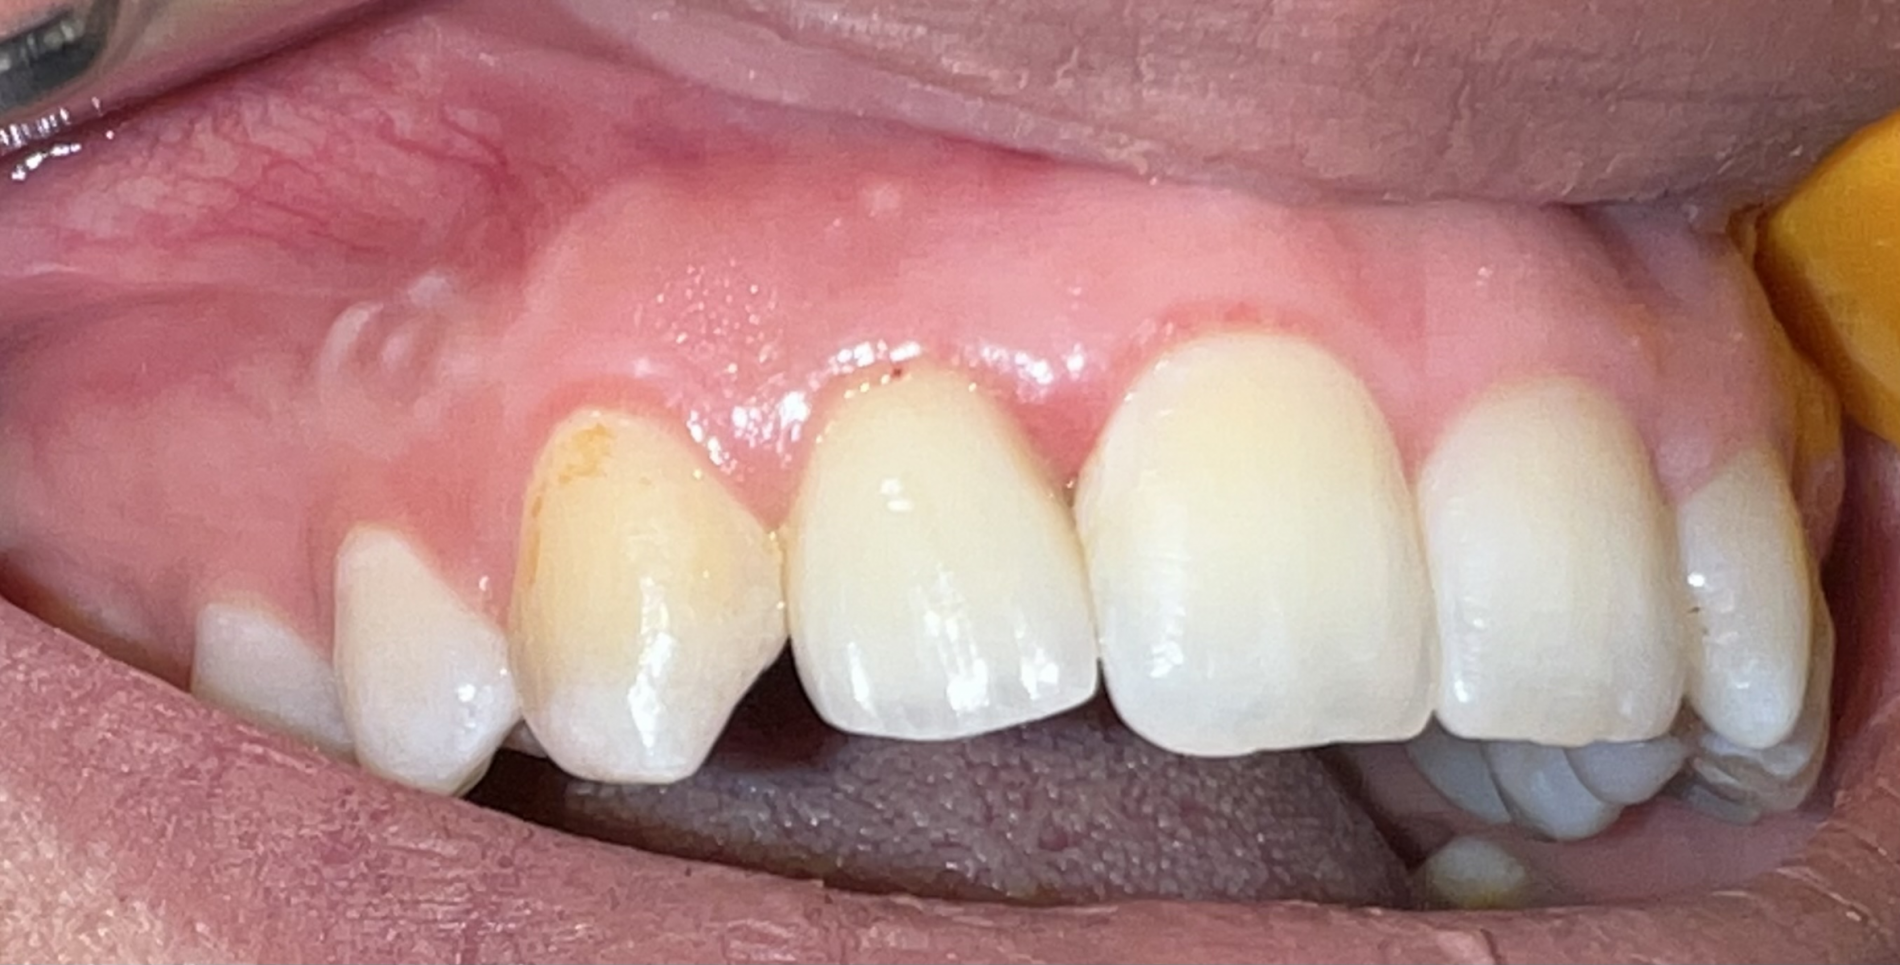

جایگزینی دندان ثنایای کناری فک بالا با ایمپلنت

جایگزینی دندان ثنایای کناری فک بالا با ایمپلنت SIC سوییس و روکش نهایی آن,فرم گرفتن طبیعی لثه در اطراف ایمپلنت و روکش.